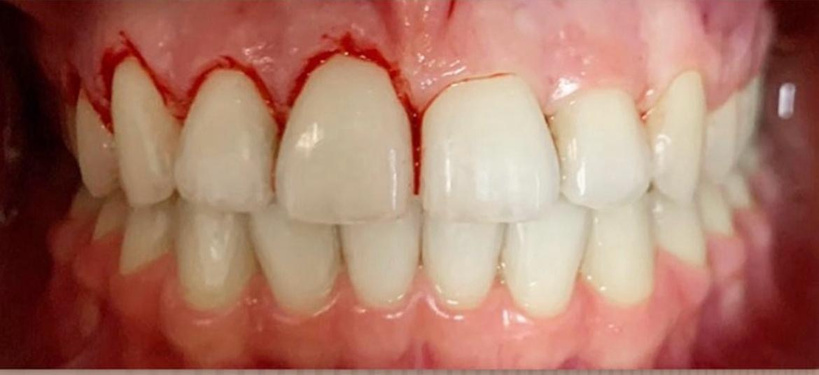

resina composta em dente anterior

curso de restaurações estéticas em resina composta

realidade clínica: resina composta